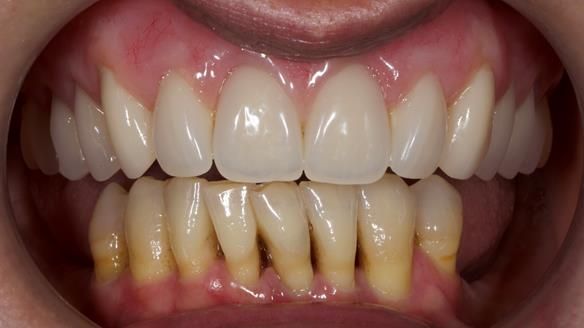

She had previously suffered from generalised periodontitis – stage IV, grade C, currently stable, with reduced attachment across the upper arch.

By the time she came to me, her periodontal condition was stable — but the aesthetics in the upper jaw were very poor.

We provided her with an immediate upper denture (Mk 1), followed by a definitive metal-based upper denture (Mk 2). A lower removable partial denture was discussed, to be made only if needed once the upper treatment was complete. However, at review, this wasn’t necessary — Adnana had excellent neuromuscular control and function, even with a shortened dental arch (SDA).